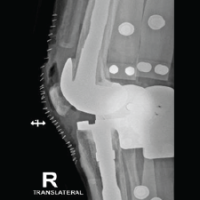

Serial radiographs showed satisfactory alignment and intact fixation of both the distal humerus and ulnar fractures. The ulnar fracture had united, while the distal humerus displayed persistent fracture lines and absence of callus formation consistent with non-union. At 6 months post-operatively, there was no bridging callus, and the fracture ends appeared atrophic (Fig. 3). Hardware remained intact, and no malalignment or implant failure was seen.

Figure 3: Six-month post-operative anteroposterior and lateral radiographs showing persistent distal humerus non-union with visible fracture lines and intact fixation hardware.

Since plain radiographs adequately defined the pathology, a CT scan was considered unnecessary. The diagnosis of aseptic atrophic non-union of the distal humerus was established.